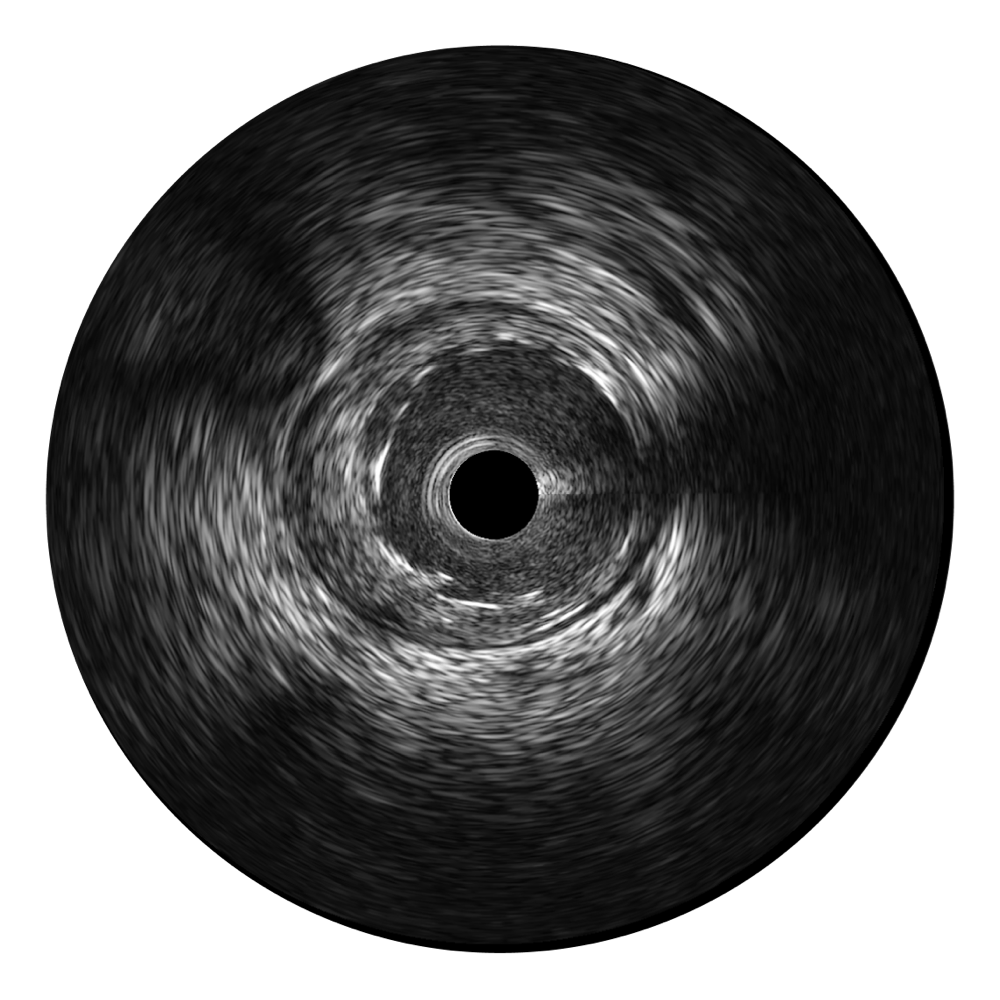

银河集团官网超宽频成像技术覆盖20-80MHz1或20-90MHz2频率范围, 提供优异的分辨力同时也保证充足的穿透深度

银河集团官网宽频IVUS图像

对比传统IVUS导管成像,银河集团官网宽频IVUS图像的近场支架梁显影更细腻,远场中膜外血管仍清晰可辨,兼顾远中近,兼顾分辨力与穿透深度